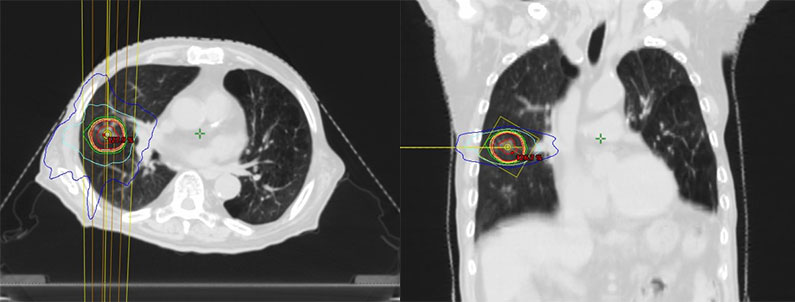

放射線治療計画

肺の定位放射線治療(SBRT)は高線量の放射線を腫瘍に正確に照射し、周囲の正常組織への影響を最小限に抑える治療法です。

手術が困難な肺がんや転移性肺腫瘍に対する有効な治療法の一つであり、肺内に限局した小さな病変や転移性病変にも用いられます。

治療の準備のためにCTを撮影します。自由に呼吸をした状態で腫瘍の動きを確認するため、四次元CT(4DCT)を撮影します。

呼吸同期照射による精度向上

腫瘍の動きが大きい場合は呼気時のみ照射を行う「呼吸同期照射」を実施します。より正確な治療が可能になり、正常肺への影響を軽減できます。